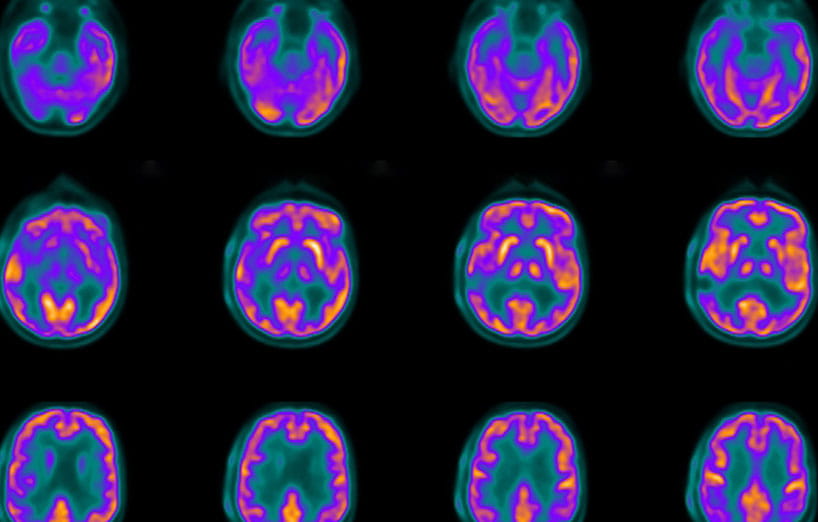

Our areas of expertise include positron emission tomography (PET), single-proton emission computed tomography (SPECT), computed tomography (CT), magnetic resonance imaging/magnetic resonance spectroscopy (MRI/MRS), ultrasound and optical imaging.

• MRI Solutions 7T 24cm large bore PET-MRI-CT/SPECT (LBPMC) scanner